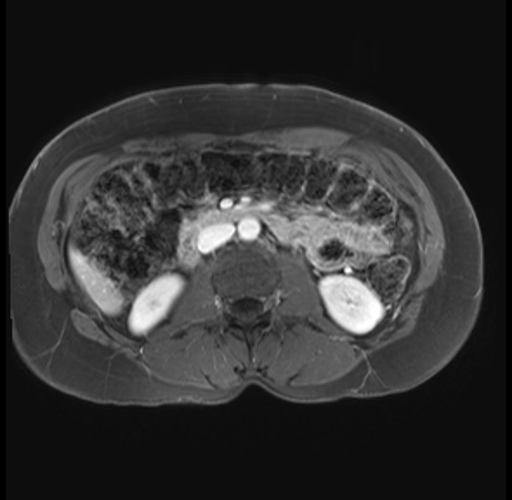

Imaging Analysis

Look through the patient's CT scan to identify any areas of concern for the necessary procedure.

Based on your CT findings, which issue(s) are present and would give reason for "planned slowing down moment(s)" in this case?